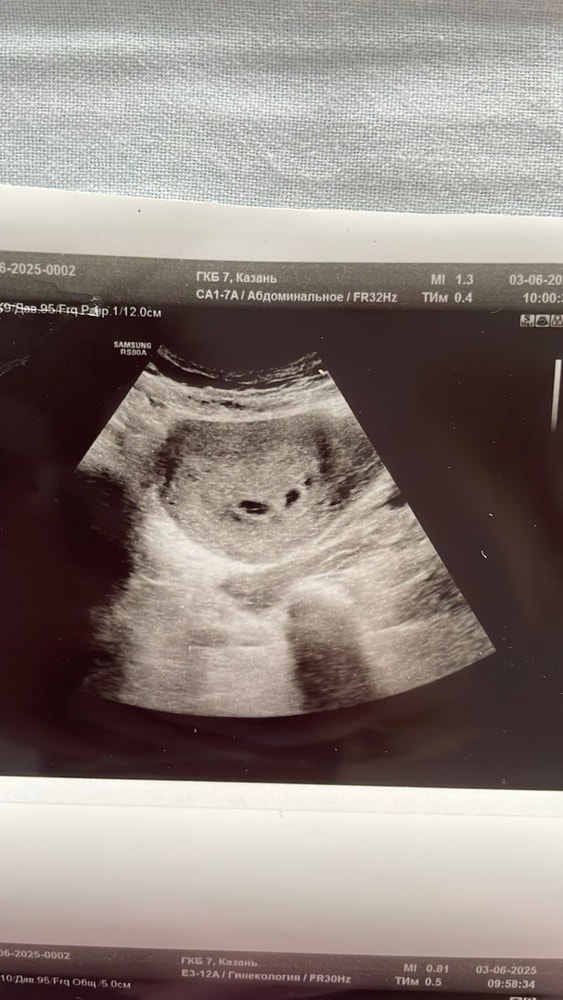

Вот мои. Справа большое пя с эмбрионом, слева рядом маленькое пустое

Татьяна, причем там еще есть несостыковки, желточный мешок виден в большом пя и замеры на снимке есть, а в описании написано, что не визуализируется.

Анастасия, моно-это одно плодное яйцо, а у меня два. Слева шарик- это второе пя. А рядом желточный с эмбрионом ( они почти одного размера) и узист пишет, первое пя, второе пя. В другой проекции они дальше находились, между ними еще расстояние было, но фото только такое